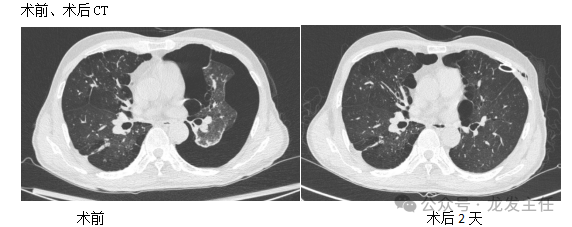

【现病史】 患者于1月余前无明显诱因出现少许咳嗽,左侧胸痛伴气喘,在外院住院治疗,予胸腔引流管引流效果不佳,反复复发。2024-9-2查胸部CT:1.左侧气胸,左肺压缩约80%-90%,左肺膨胀不全。2.考虑慢性支气管炎、肺气肿征,双肺散在纤维增殖钙化灶、多发肺大疱。诊断:1、难治性气胸2、慢性阻塞性肺疾病3、多发肺大疱。

【治疗过程】诊疗经过:9月2日行胸腔镜下胸膜粘连松解术+胸腔镜下肺大疱治疗,术后气胸、胸痛症状较前好转,无气喘。